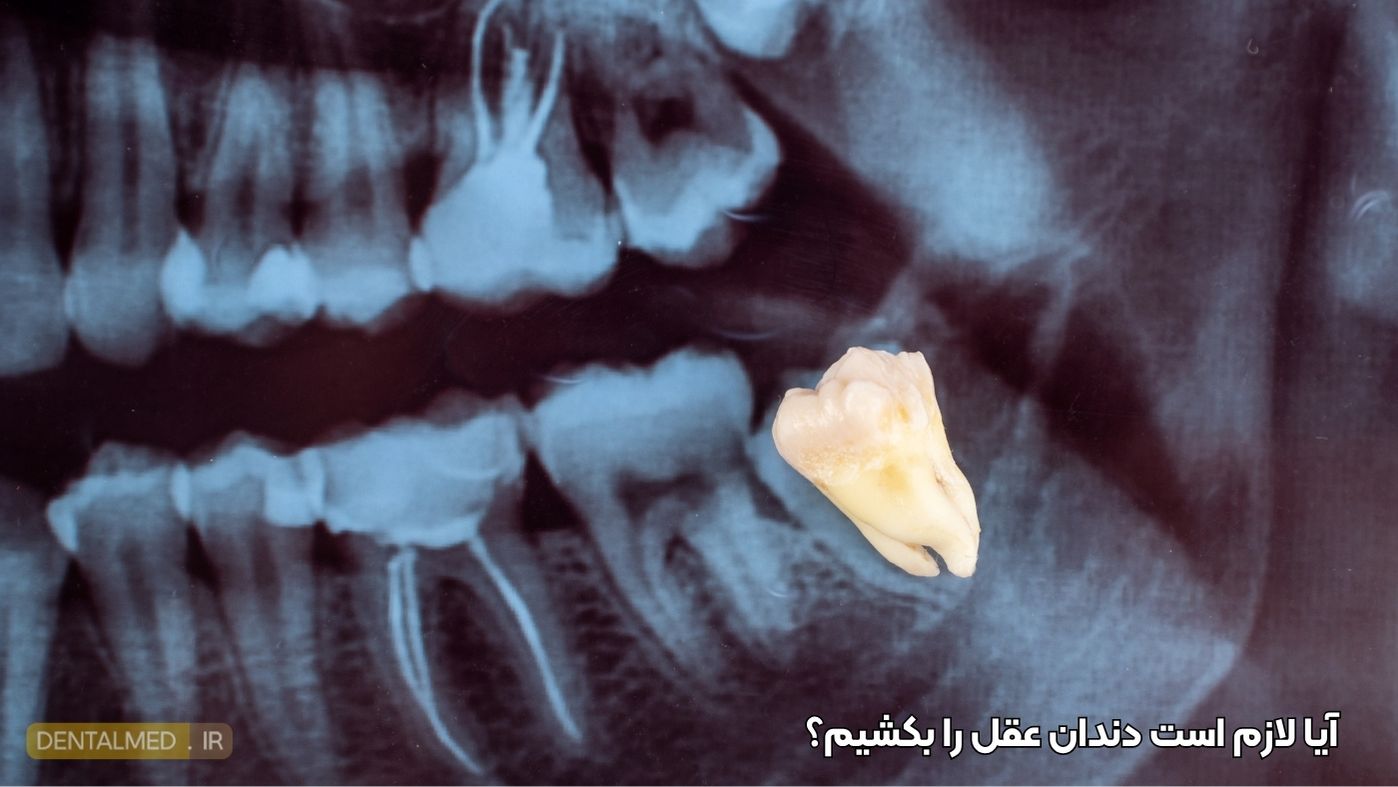

آیا لازم است دندان عقل را بکشیم؟

در همه موارد، کشیدن دندان عقل ضروری نیست. اگر دندان عقل شما کاملاً روییده، سالم و بدون درد باشد، ممکن است نیازی به جراحی یا کشیدن آن نباشد.اما اگر در ناحیه دندان عقل احساس درد، تورم یا ناراحتی دارید، حتماً باید در اولین فرصت به دندانپزشک مراجعه کنید تا وضعیت دقیق دندان بررسی شود.

براساس داده های قدیمی ذکرشده در یک مقاله در سال ۲۰۰۷، حدود ۸۵٪ از افراد در طول زندگی خود حداقل یک دندان عقل را به دلیل مشکلاتی مانند نهفتگی، عفونت یا ناهماهنگی فکی میکشند. همچنین حتی اگر دندان عقل شما در حال حاضر مشکلی ایجاد نکرده باشد، ممکن است دندانپزشک برای جلوگیری از بروز مشکلات آینده، کشیدن آن را به صورت پیشگیرانه توصیه کند.